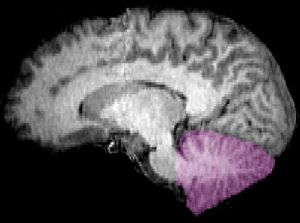

很久以来人们一直以为小脑的主要功能是支配肢体动作协调性。然而本月发表在《神经元》(Neuron)期刊上的研究发现,小脑的作用可远不止这个方面,小脑“插手”高层次大脑功能的几乎每个方面,包括注意力、思考、计划和决策,扮演着最后审查这些大脑活动的角色。

他们在小脑中找不到关于感官处理的网络,比如视觉、听觉和触觉,只有20%的小脑致力于控制肢体行动,这与大脑皮层的情况类似。小脑剩余80%的功能都在处理高级认知任务:控制注意力;和没有特别集中注意力时候的工作,比如做“白日梦”、回味记忆、或漫无目的“胡思乱想”;以及执行监控决策和计划功能。

该研究的首要作者Scott Marek说:“小脑的高层决策功能占有很大的比重,我们对小脑的认知要从以前认为的主要协调运动,转变为更多是控制高层次认知这一方面。”